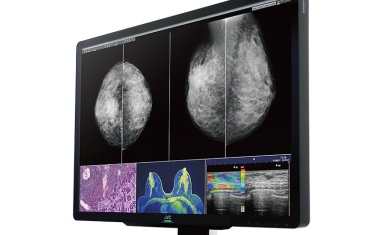

Konferenzsystem mit höchster Bildqualität zur Förderung des interdisziplinären Austauschs bei komplexen Fällen